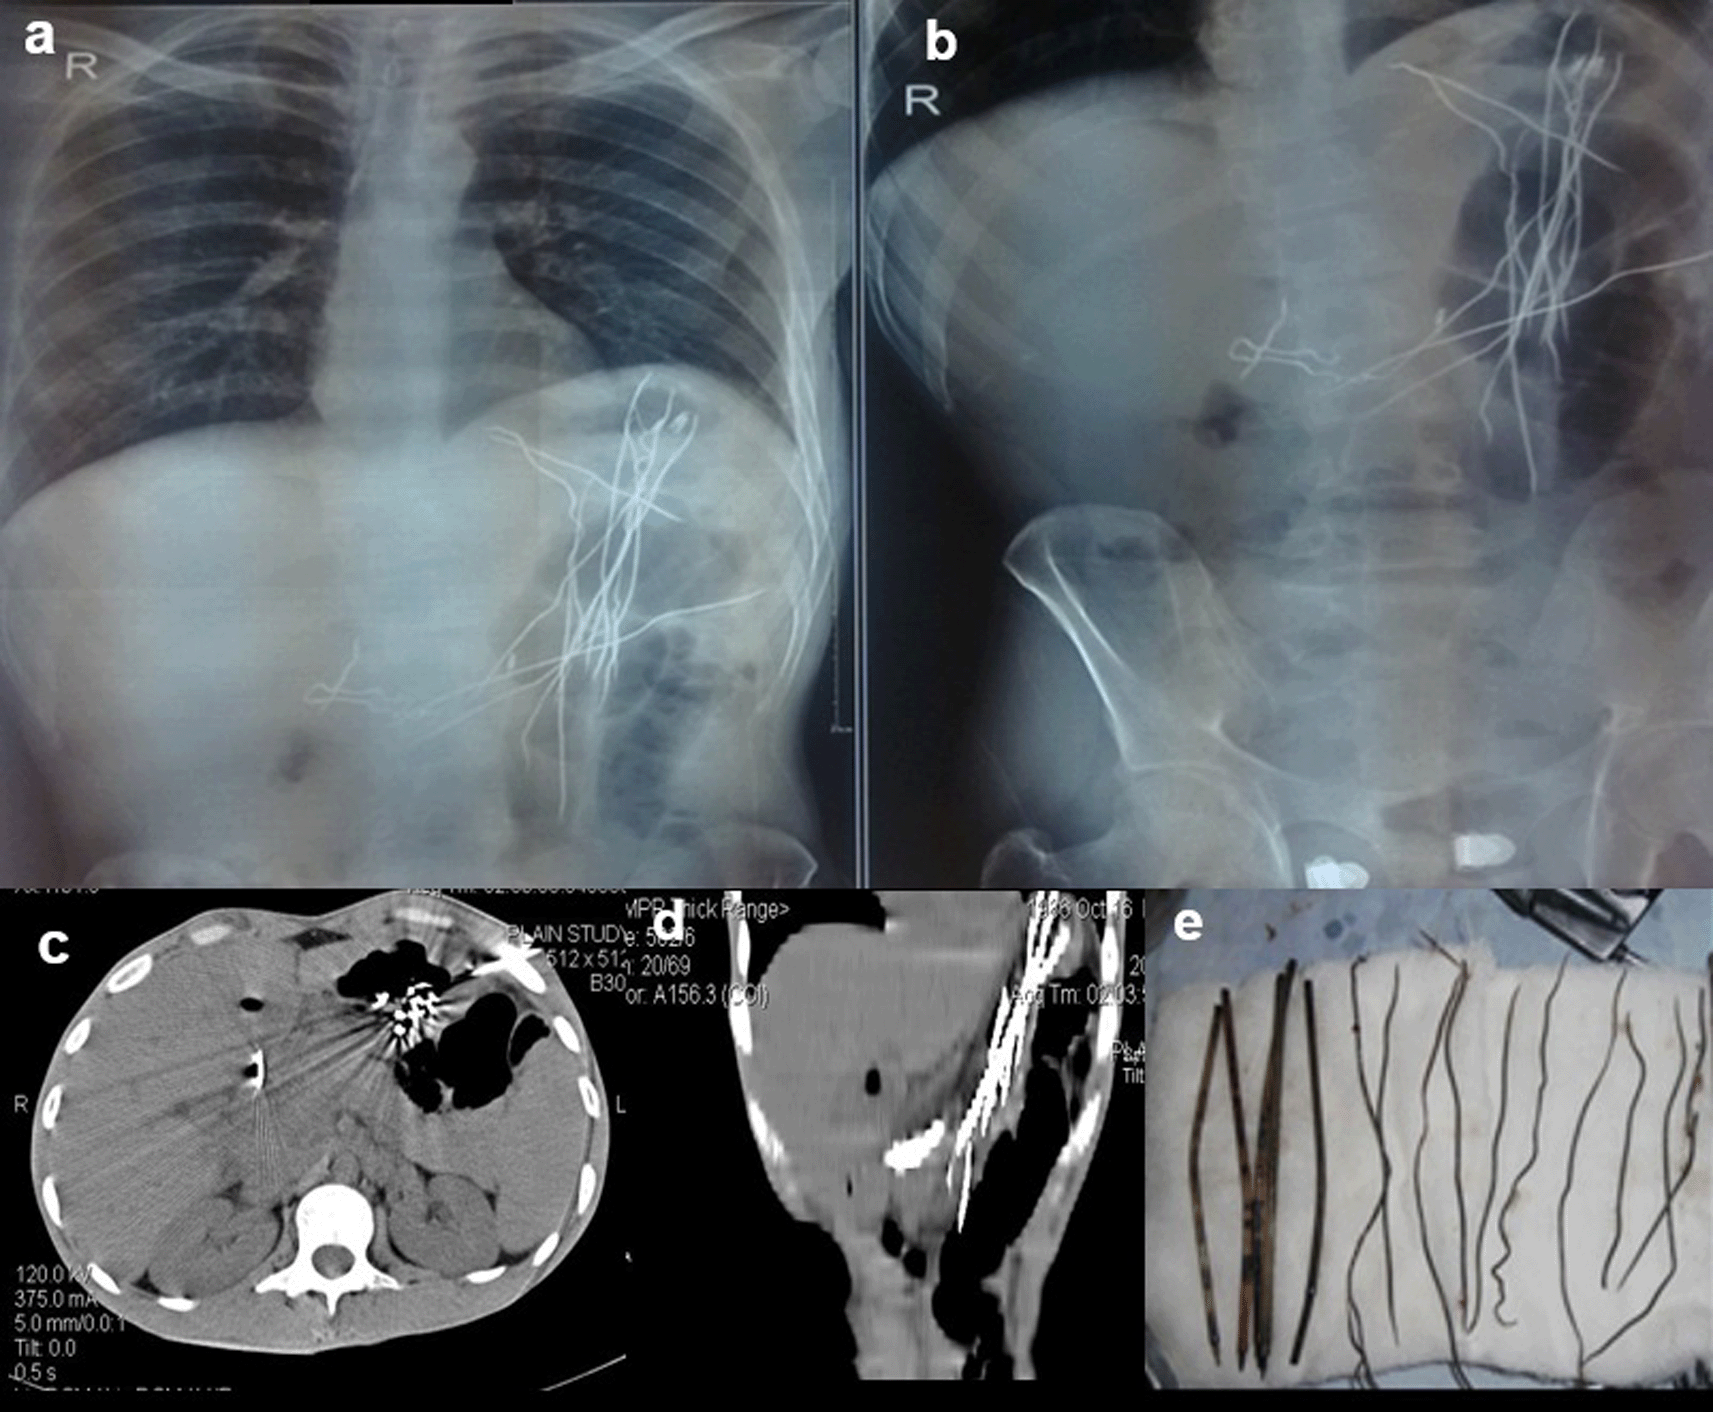

Case 3: A 25-year-old male patient came for ultrasound examination with complaints of pain in the abdomen for two-three months. Radiograph of the chest and abdomen reveal multiple linear radio-opacities in the left hypochondriac and lumbar quadrants of the abdomen, and a plain CT scan shows multiple hyperdense linear metallic foreign bodies within the gastric lumen, many piercing the gastric wall partially without any evidence of perforation. On laparoscopy, multiple refills of the pen and wires were found in the stomach, which were removed.

The swallowing of foreign bodies is a common condition in children and mentally challenged individuals.3–5 Fortunately, most ingested objects move through the digestive system without causing any problems (Figure 1a,b). Sharp and elongated objects can pass uneventfully (Figure 2a,b); however, they can pierce the mucosal lining and seriously damage or completely perforate the intestinal wall (Figure 3a-e). The object may just partially puncture the gut wall, resulting in a chronic inflammatory condition with few symptoms that is diagnosed months or years later.5–7

On laparoscopy, multiple refills of the pen and wires were found in the stomach, which were removed (e).

When a patient cannot provide a sufficient history or has swallowed things that are not naturally radio-opaque, the diagnosis of an ingested foreign body is frequently missed. If a foreign body is suspected and is not visible on a Radiograph because of its radiolucent nature, a CT scan of the abdomen or chest may be beneficial8 (Figure 4a,b).